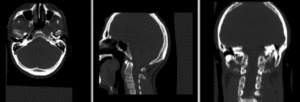

- Head & Neck 3DCT inter-subject

- 2010_Summer_Project_Week_HandN_Cancer

- initial discussion with Marta: issues with stopping criterion, FOV and DOF constraints, both inter- and intra-subject registration; collecting dataset for trials. PM: Precision ***, Speed *, Robustness **